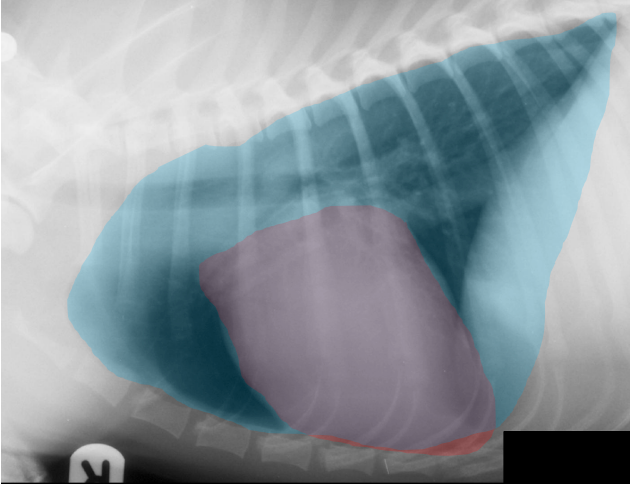

Estómago e Hígado Radiografia Laterolateral y Ventrodorsal

- Eje estómago: perpendicular a la CV, paralelo a las costillas o en una posición intermedia

- Hígado: tamaño, contorno, localización y densidad